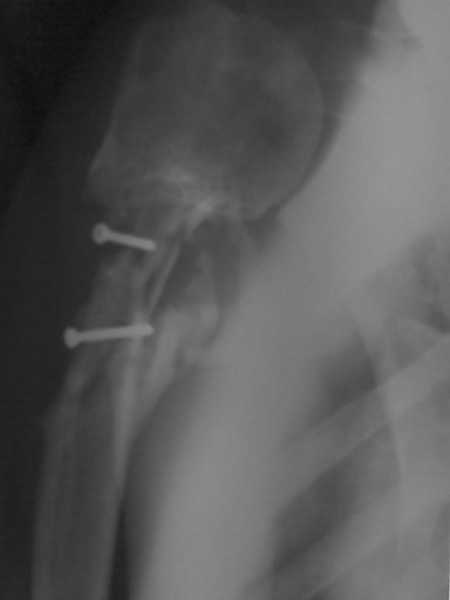

[Ortho] Ложный сустав в/3 плечевой кости!

Здравствуйте, коллеги!!! К нам в отделение госпитализирован пациент 39 лет с

клинико-рентгенологической картиной ложного сустава в/3 плечевой кости! Снимки

прилагаются! Предистория такова: около года назад получил оскольчатый перелом в/3

плечевой кости. В одной из московских больниц выполнен остеосинтез пластиной, через

несколько месяцев выполнен реостеосинтез, опять же пластной...., причины реостеосинтеза

со слов пациента таковы - "доктору не понравилась как лежит пластина и он ее переложил..." -

два месяца назад выполнено удаление фиксатора. Никаких выписок у больного нет. Около недели

обратился в травмопункт, откуда направлен к нам. Клинически у пациента имеется подвижность

в области в\3 плеча, костная крепитация, умеренная болезненность в в/3 плеча при движениях,

атрофия дельтовидной мышцы. На следующей недели планируем пациента опериравать. Коллеги,

у нас возникло несколько вопросов, если не затруднит, то посоветуйте и подскажите... Мы

планируем выполнить закрытый блокируемый остеосинтез, скажите пожалуйста, нужно ли в этом

случае, на ваш взгляд, выполнять костную пластику или достаточно выполнить рассверливание

костномозгового канала и заштифтовать толстым гвоздем, нужно ли пытаться удалить винты???